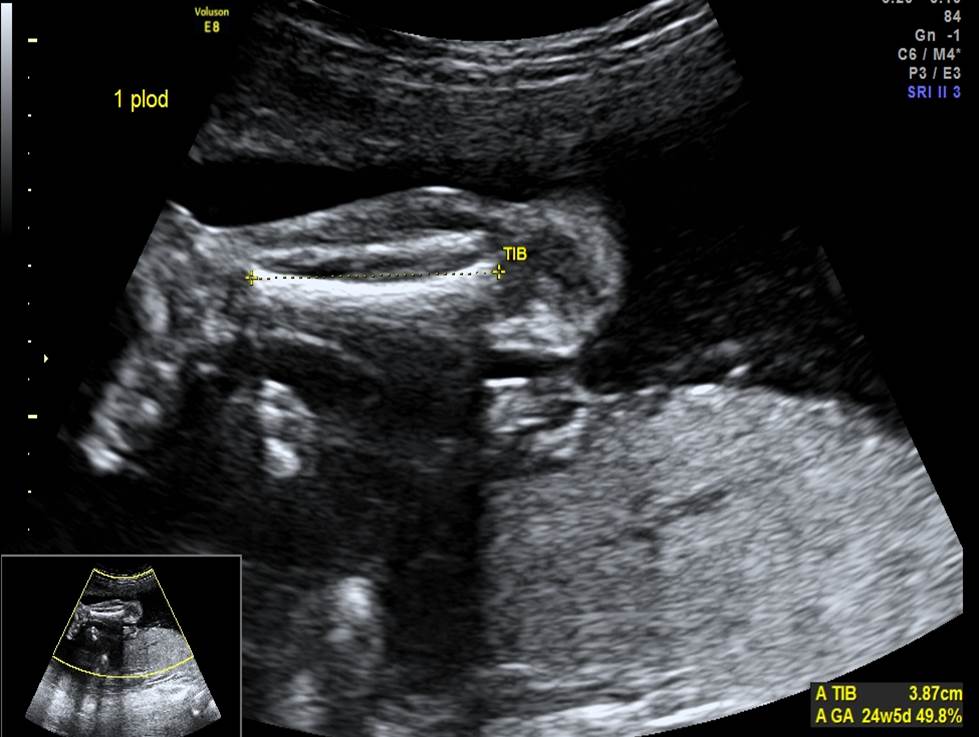

Проанализируйте изображения первого плода из дихориальной двойни в 24 недели (плод мужского пола), установите диагноз и дальнейшую тактику ведения беременности